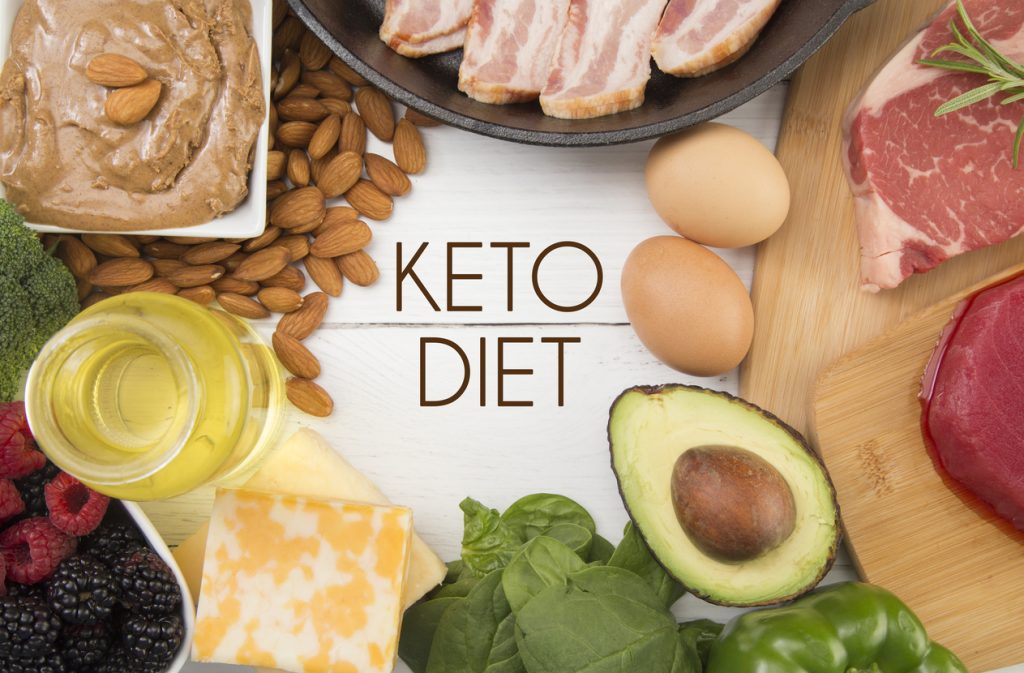

ΡΟΦΗΜΑΤΑ

PRONEWS.GR / Υγεία

Αυτά τα ροφήματα οδηγούν στην αύξηση του βάρους σας

PRONEWS.GR / Υγεία